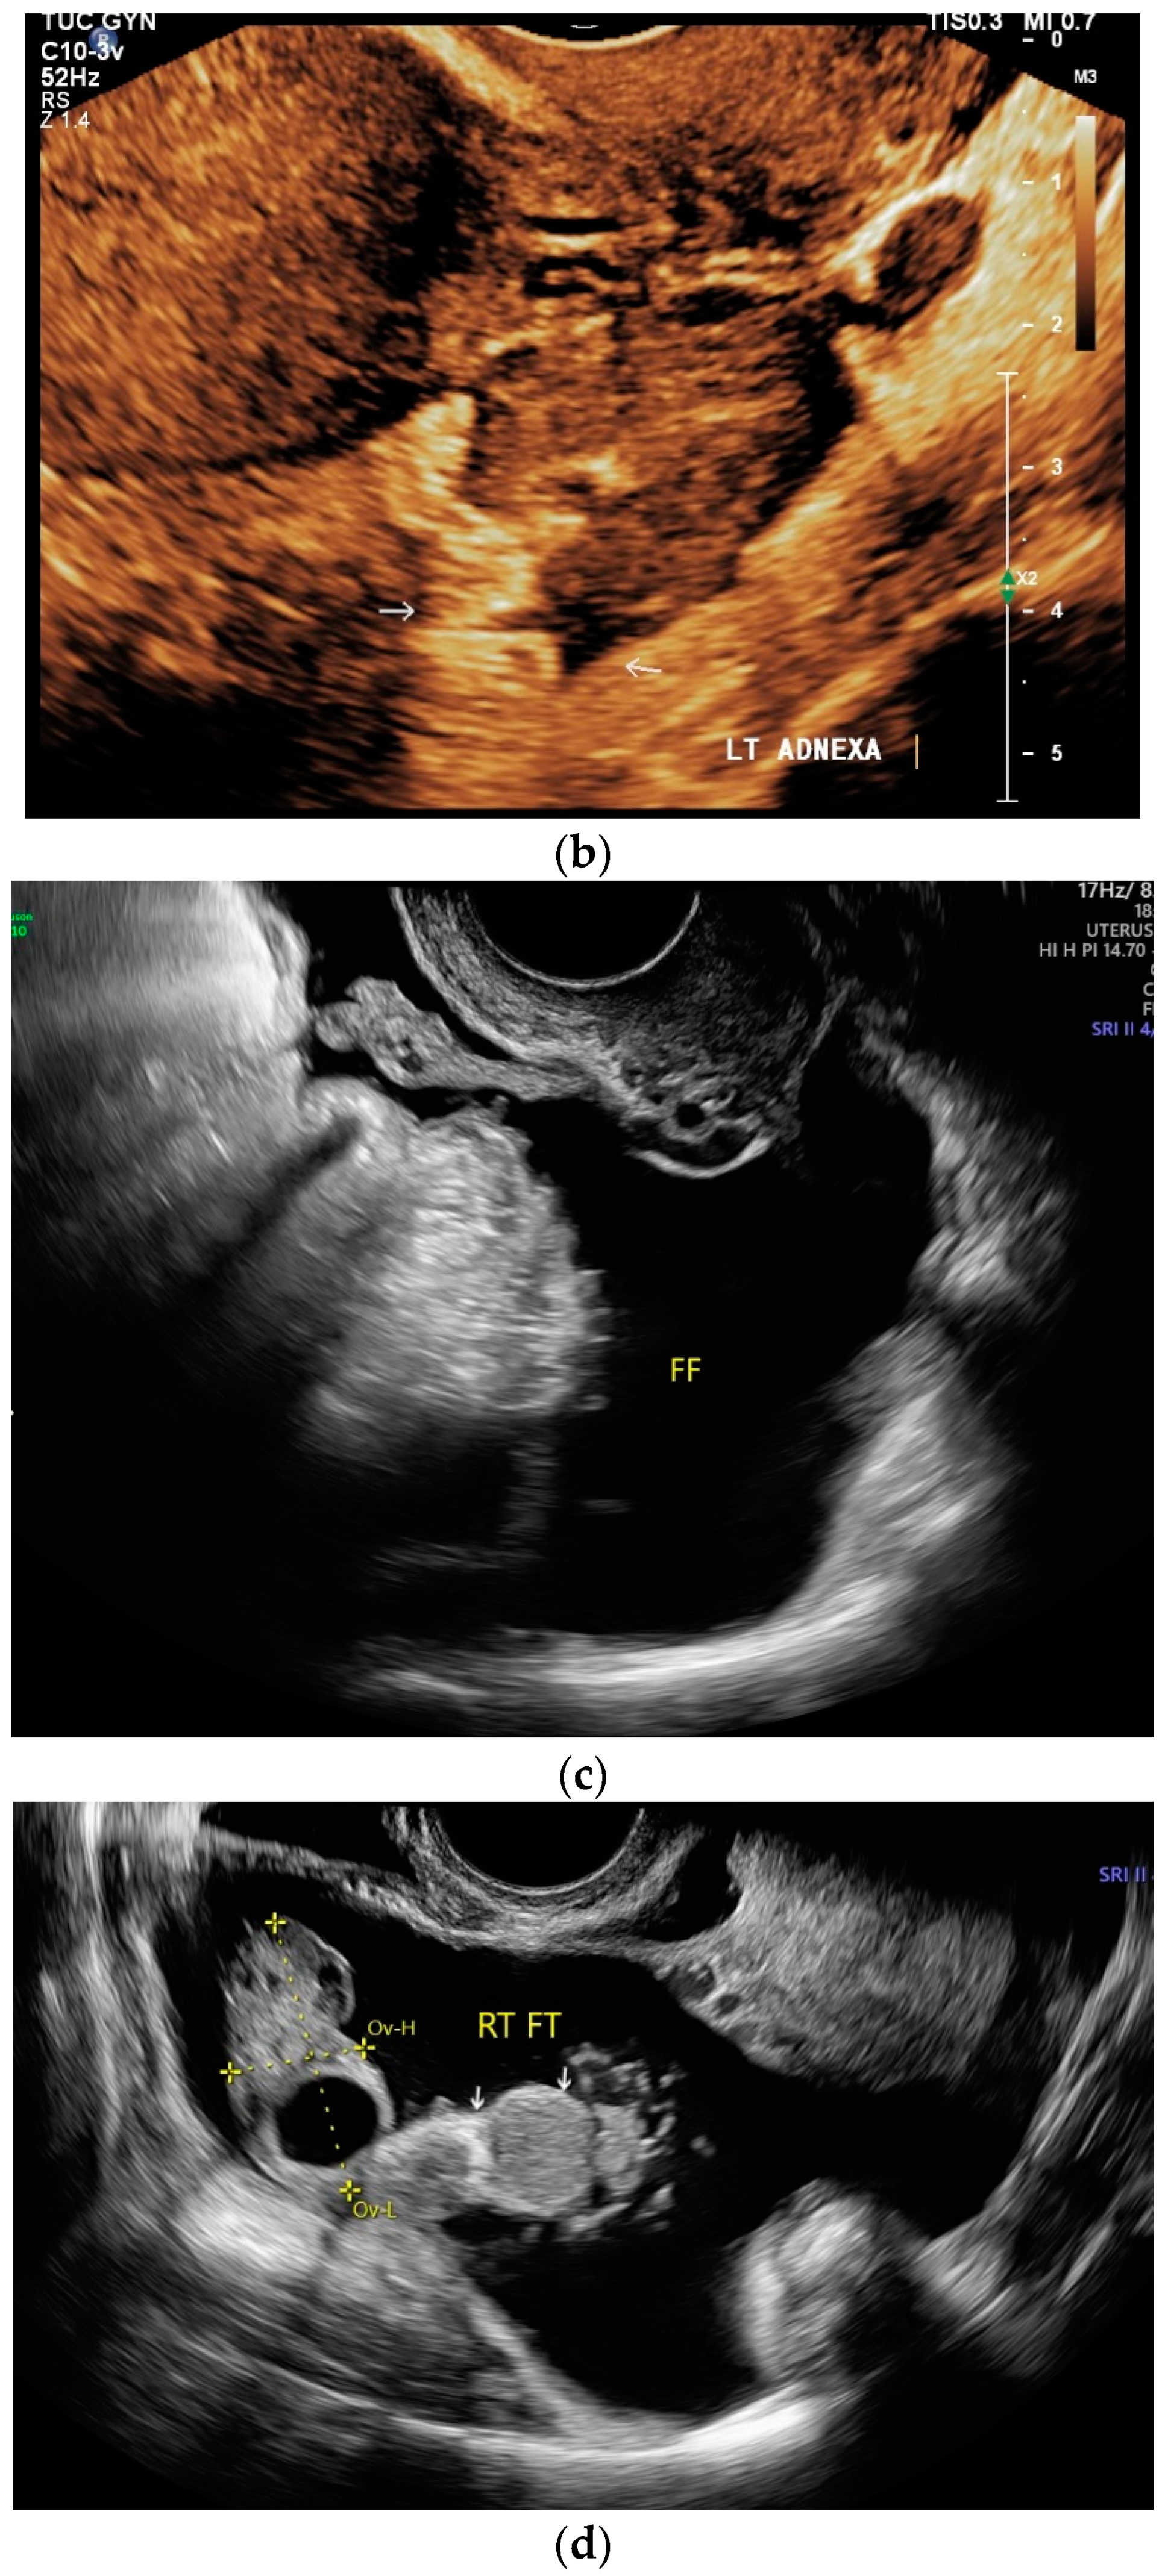

Papillary necrosis can occur, caliectasias develop in the course of the disease, and some patients develop hydronephrosis [114]. Caliectasia can present as asymmetric hydrocalicosis [115] [Figure 7a,b].

Figure 7.

Renal tuberculosis. Adjacent to the renal sinus are cyst-like lesions with smooth borders. Characteristic of caliectasias (a). Small “tubular” structures are noticeable in the kidney (arrow). The parenchyma presents nodular hypoechoic lesions. Perforation of caseous necrosis, and small intrarenal fistulas (b). “Putty kidney”—final stage of renal tuberculosis. Very small (non-functioning) kidney with highly diffused hyperechoic parenchyma (c), surrounded by a perinephritis fluid collection (d).

“Putty kidney” is a possible final stage of renal tuberculosis. The term describes diffuse parenchymal renal calcifications that can be seen on a simple X-ray, as well as a “putty-like” substance, which is found inside a surgically removed tuberculosis kidney [117,118] [Figure 7c,d].

If the ureter is affected, mucosal irregularities and ureteral dilatation due to localized or multilocular strictures must be differentiated in radiological imaging. The ureter can shorten (pipe-stem ureter) [114]. Varied effects of tuberculosis on the urinary tract are infundibular stenosis with caliectasis, moth eaten calyx, parenchymal calcification, cortical scarring, caseous mass/abscesses (with potential rupture into the perinephritic space and calyx) [Figure 7b], a hiked-up pelvis, urothelial thickening, and a beaded ureter [115].